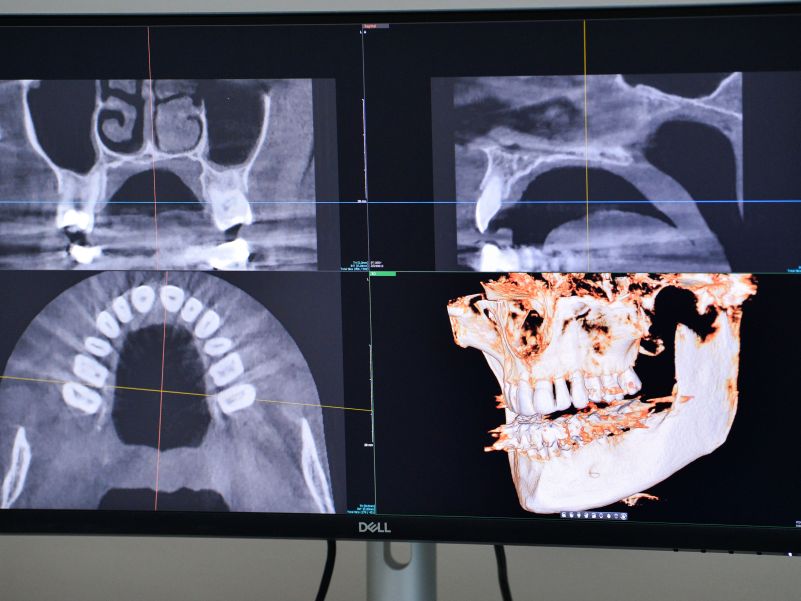

Snimanje zuba i vilica je ključni korak u stomatološkoj dijagnostici i planiranju odgovarajućeg tretmana. Ova tehnika omogućava stomatolozima dublji uvid u oralno zdravlje pacijenata, što ima brojne prednosti, kao što su uspostavljanje precizne dijagnostike, planiranje tretmana, prevencija problema, smanjenje rizika kao i lakše praćenje napredka.

Uz to, snimci zuba i vilice pružaju vizuelnu ilustraciju stanja pacijentima, što im pomaže da bolje razumeju svoje oralno zdravlje i tretmane koje je potrebno sprovesti.

U X Dent-u radimo na najmodernijim digitalnim aparatima što nam omogućava da izradimo snimke vrhunskog kvaliteta, a da pri tome pacijenta izložimo minimalnom mogućem zračenju.